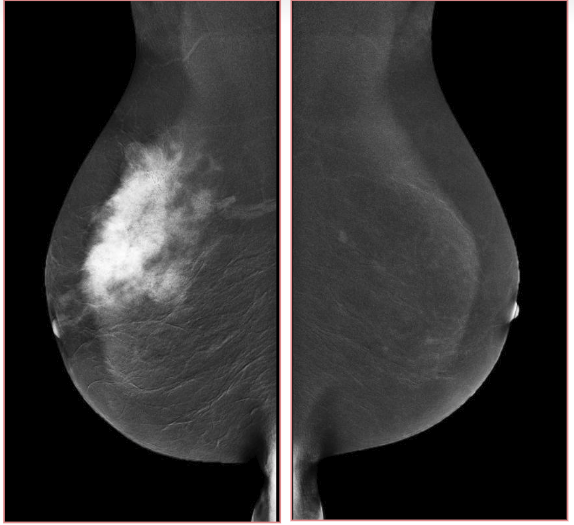

Digital breast tomosynthesis (DBT) is a promising new technology for acquiring and displaying three-dimensional mammograms [17]. Because of its improved ability to differentiate true breast lesion or summation of normal breast structures. An example image of tomosynthesis is shown in Fig. 3, for the different planes, it has improved characterization of masses. Tomosynthesis is increasingly being used in the diagnostic setting to evaluate masses, asymmetries, and architectural distortion. Tomosynthesis can be done in full or spot compression views as needed [18]. The sensitivity and specificity of DBT ranged from 74.2% to 86.9% and 97.0% to 97.5%, respectively [19].